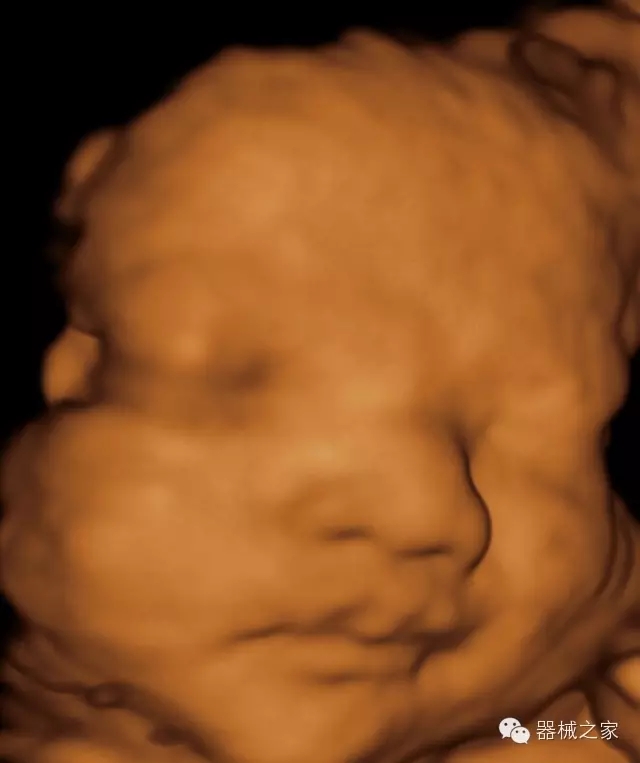

·完整的3D/4D臨床應(yīng)用,STIC, MCUT 和Auto NT等滿足產(chǎn)科所有應(yīng)用;

·更高的HQ羊膜腔鏡成像技術(shù)精細觀察每一個暗區(qū)細節(jié);

·智能的觸摸屏界面,能任意角度方位旋轉(zhuǎn)3D圖像,以及注釋快速標(biāo)記,提供直觀與便捷的操作,提高了工作效率;

·高效3D/4D成像技術(shù):高速的4D幀頻,豐富的3D成像模式,智能斷層切片功能;